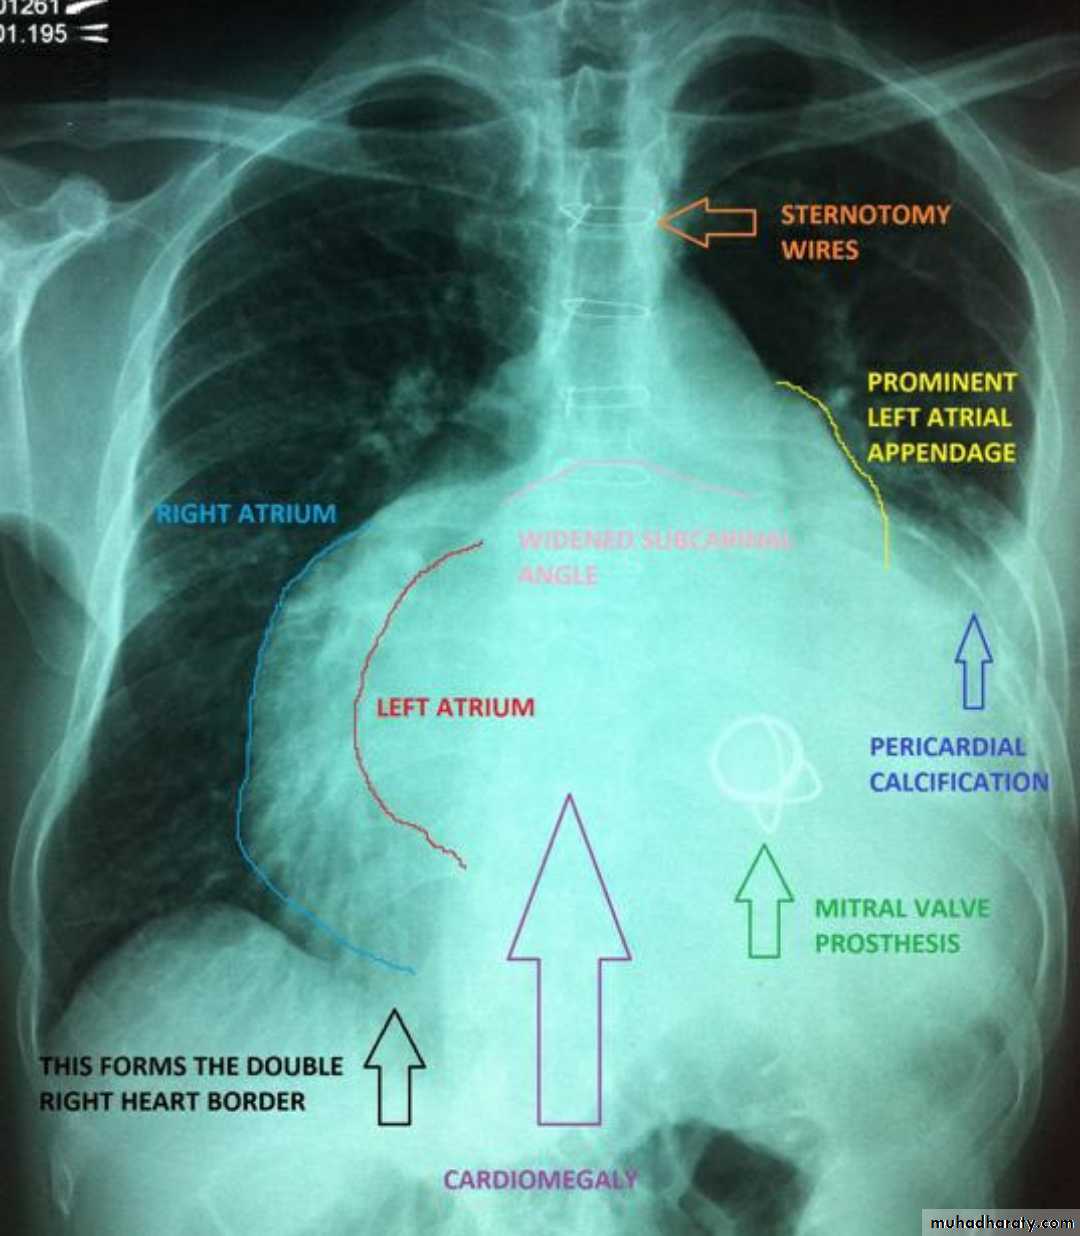

Mitral valve diseaseCXR of adult male , PA view shows: Enlargement of the cardiac shadow (cardiomegaly), Enlargement of left atrium Double density sign: the right side of the enlarged left atrium pushes into the adjacent lung and creates an addition contour superimposed over the right heart.

Mitral valve disease (double density RT cardiac border)CXR of adult , PA view shows: Cardiomegally Double density sign of right cardiac border Enlargement of left atrium, permenant left atrial appendage and relaced mitral valve (prosthesis)